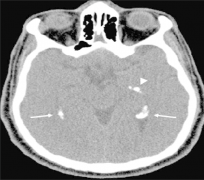

听神经瘤 多数发生于听神经的前庭神经,随着肿瘤生长变大,压迫桥脑外侧面和小脑前缘,充满于小脑桥脑角内。听神经瘤占颅内肿瘤的8.43%。好发于中年人,高峰在30-50岁。病程相对...

听神经瘤属于良性肿瘤(非恶性也非癌),通常生长缓慢,平均年增长率为2mm,听神经瘤的发病率每年约为1/10万人,早期诊断常有困难。 听神经瘤常被认为是脑肿瘤,但其实并不位于...

听神经瘤 ,更准确地说是前庭神经鞘瘤,是一种生长在平衡和听力神经上的良性肿瘤。这些神经缠绕在一起形成前庭耳蜗神经,从内耳到大脑。由听神经瘤引起的听力损失通常只发生在...